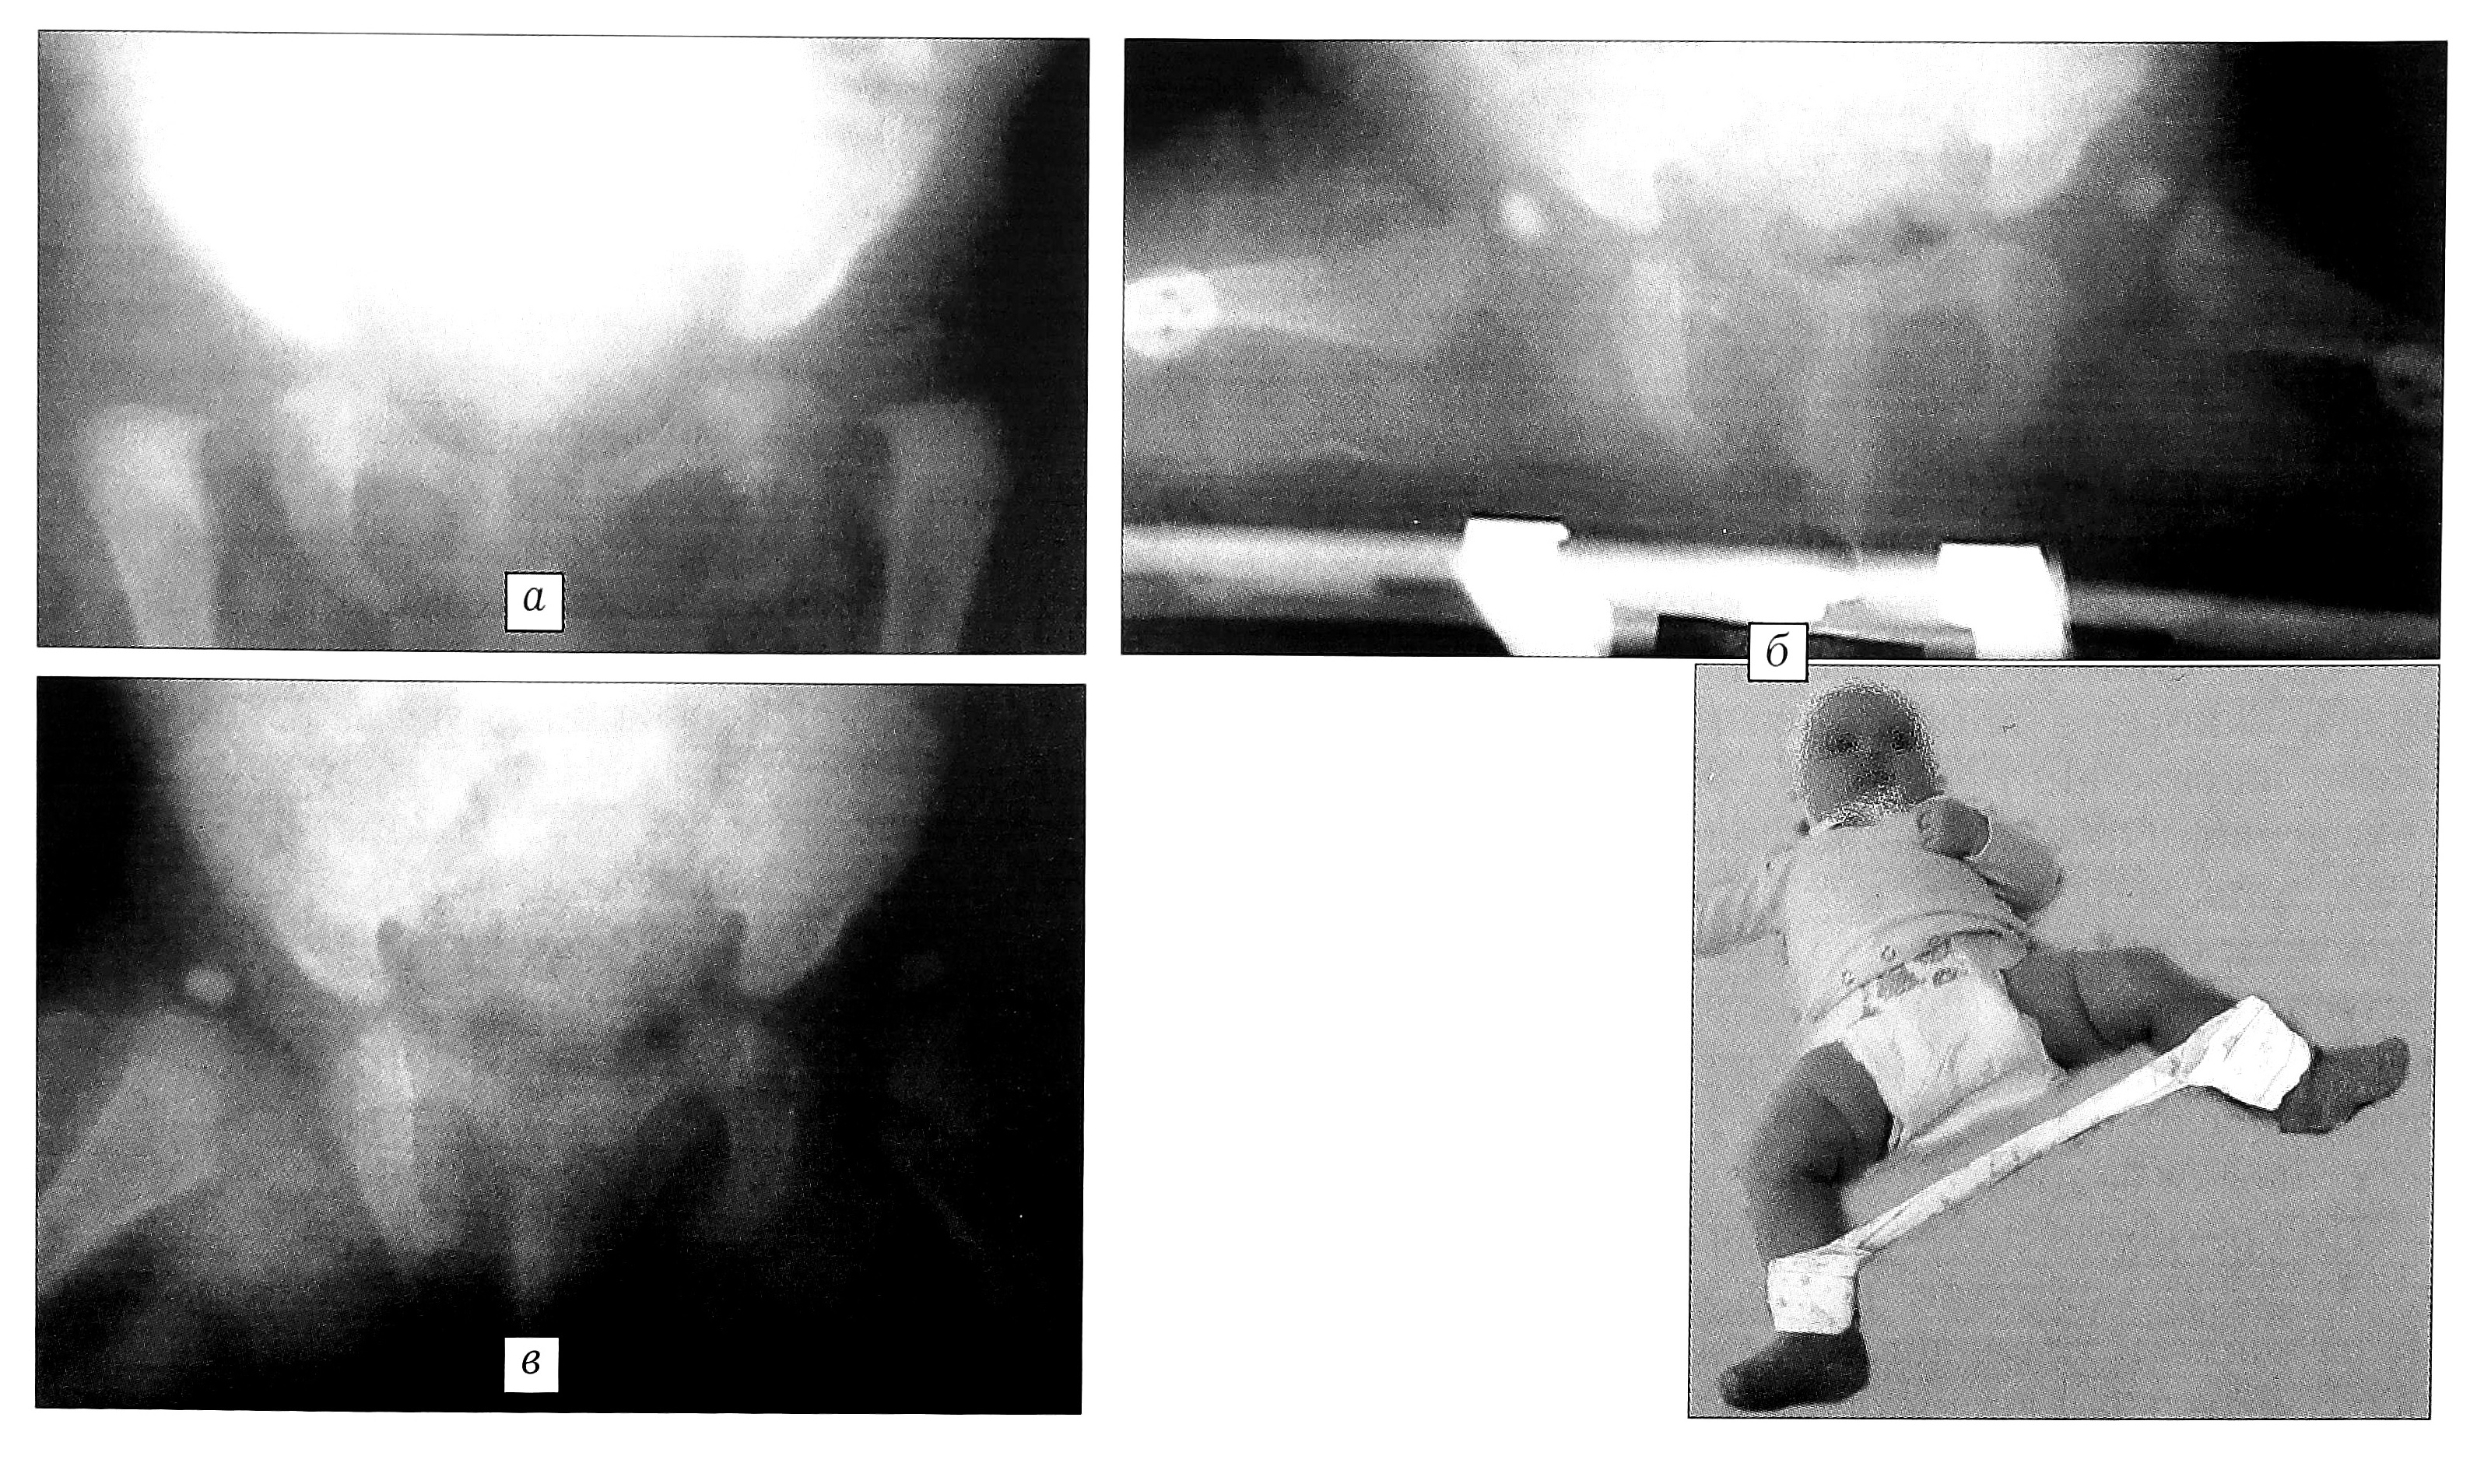

Для сравнения приведем отдаленные результаты лечения двух пациентов из разных групп: у больной первой группы (рис. 6) сустав в дальнейшем своем развитии приближается к нормальному, тогда как у больной второй группы (рис. 7) отмечается нарушение формирования сустава, проявляющееся как деформацией головки бедра, так и недоразвитием элементов сустава. Из этого следует, что при практически равной первоначальной степени дисплазии и одинаковом возрасте успешного вправления вывихов тазобедренные суставы у пациентов двух выделенных групп развиваются по-разному.

Рис. 6. Отдаленный результат лечения больной В. (первая группа). а — в возрасте 8 мес: ацетабулярный вывих головок бедренных костей; б — лечение в функциональной гипсовой повязке: через 1 мес после начала лечения достигнуто вправление; в — в возрасте 1 года 6 мес: развитие тазобедренных суставов соответствует возрастной норме; г — клинико-рентгенологический результат в возрасте 10 лет: полная компенсация функции тазобедренных суставов.

Рис. 7. Отдаленный результат лечения больной Д. (вторая группа). а — в возрасте 4 мес: ацетабулярный вывих головок бедренных костей; б — в возрасте 7 мес: неадекватное лечение в отводящей шине (до поступления в ЦИТО), головки бедренных костей располагаются вне вертлужных впадин; в — в возрасте 9 мес: при лечении в функциональной гипсовой повязке достигнуто вправление; г — в возрасте 1 года 9 мес: развитие тазобедренных суставов соответствует возрастной норме; д — клинико-рентгенологический результат в возрасте 13 лет: субкомпенсация функции тазобедренных суставов; формирование остаточного подвывиха головок бедренных костей, больше выраженное справа.